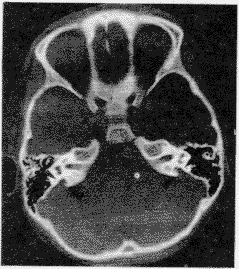

愛滋病在耳鼻咽喉-頭頸部的表現 愛滋病患者約有40%—70%出現耳鼻咽喉-頭頸部病變。

1、耳部病變 Kaposi肉瘤為多發性出血性肉瘤,可發生於外耳,表現為紅紫色斑塊或結節,外耳的卡氏肺囊蟲感染為多核性囊腫,病檢可發現原蟲,盯聹中尚未發現病毒,但可從鼓室積液中分離出HIV,中耳農業中培養可見到真菌、原蟲、病毒或分布桿菌,HIV易侵犯中樞神經系統或聽神經,早期感音神經性聽力減退較為常見。

2、鼻及鼻竇病變 鼻腔和鼻竇黏膜可因阿米巴原蟲等感染而引起黏膜腫脹,產生鼻塞,流膿涕或鼻出血等症狀,鼻部的皰疹病毒感染可產生巨大皰疹性潰瘍,自鼻前庭向外擴展至鄰近的鼻翼等處,KS也可發生於鼻部。

3、口腔及咽喉病變 口腔和咽部的念珠菌感人是最常見的上呼吸道病變,多見於舌的腹面,亦可發生於咽部或食管,引起咽痛和吞咽困難,病變表便有假膜形成,除去假膜可見粗糙紅斑樣創面,其能產生內毒素及酶,可穿透黏膜波及深層,茸毛狀黏膜白斑常見於舌的腹面或側緣,為粗厚的白色突起,多固著於上皮表面,據報導,在茸毛狀黏膜白斑病確診後,有48%的病人在16個月之內發展為愛滋病,83%的病人在31個月之內發展為愛滋病,有時咽部可見白色乳酪樣的真菌感染,形成部分阻塞,黏膜可因真菌的經常刺激而角化,呈現白斑樣的粗糙表現,經真菌鏡檢查或培養可確診。愛滋病患者的扁桃體言可由常見致病菌,肺炎支原體和沙眼衣原體等所引起。KS常發生在齶部、頰黏膜、牙齦黏膜和咽後壁,KS和念珠菌感染亦可發生於喉部,導致聲嘶,喉喘鳴和喉阻塞。

4、頸部病變 頸淋巴結病變是早期症狀之一,由於HIV感染導致濾泡增生,常有頸淋巴結腫大,KS可發生於頭頸部的皮膚,當其侵犯淋巴結時,頸淋巴結可迅速增大,頸部腫塊還應考慮非何杰金淋巴瘤及分布桿菌感染等。細針穿刺抽吸活檢(FNAB)有助於診斷和鑑別診斷。頭頸部磷狀細胞癌在愛滋病患者亦較多見,其他還可有病毒等感染所致的腮腺腫大等。